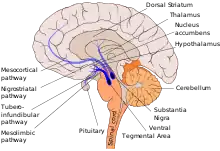

The mesolimbic pathway, sometimes referred to as the reward pathway, is a dopaminergic pathway in the brain.[1] The pathway connects the ventral tegmental area in the midbrain to the ventral striatum of the basal ganglia in the forebrain. The ventral striatum includes the nucleus accumbens and the olfactory tubercle.[2]

The mesolimbic pathway is a collection of dopaminergic (i.e., dopamine-releasing) neurons that project from the ventral tegmental area (VTA) to the ventral striatum, which includes the nucleus accumbens (NAcc) and olfactory tubercle.[9] It is one of the component pathways of the medial forebrain bundle, which is a set of neural pathways that mediate brain stimulation reward.[10]

The VTA is located in the midbrain and consists of dopaminergic, GABAergic, and glutamatergic neurons.[11] The dopaminergic neurons in this region receive stimuli from both cholinergic neurons in the pedunculopontine nucleus and the laterodorsal tegmental nucleus as well as glutamatergic neurons in other regions such as the prefrontal cortex. The nucleus accumbens and olfactory tubercle are located in the ventral striatum and are primarily composed of medium spiny neurons.[9][12][13] The nucleus accumbens is subdivided into limbic and motor subregions known as the NAcc shell and NAcc core.[11] The medium spiny neurons in the nucleus accumbens receive input from both the dopaminergic neurons of the VTA and the glutamatergic neurons of the hippocampus, amygdala, and medial prefrontal cortex. When they are activated by these inputs, the medium spiny neurons' projections release GABA onto the ventral pallidum.[11]